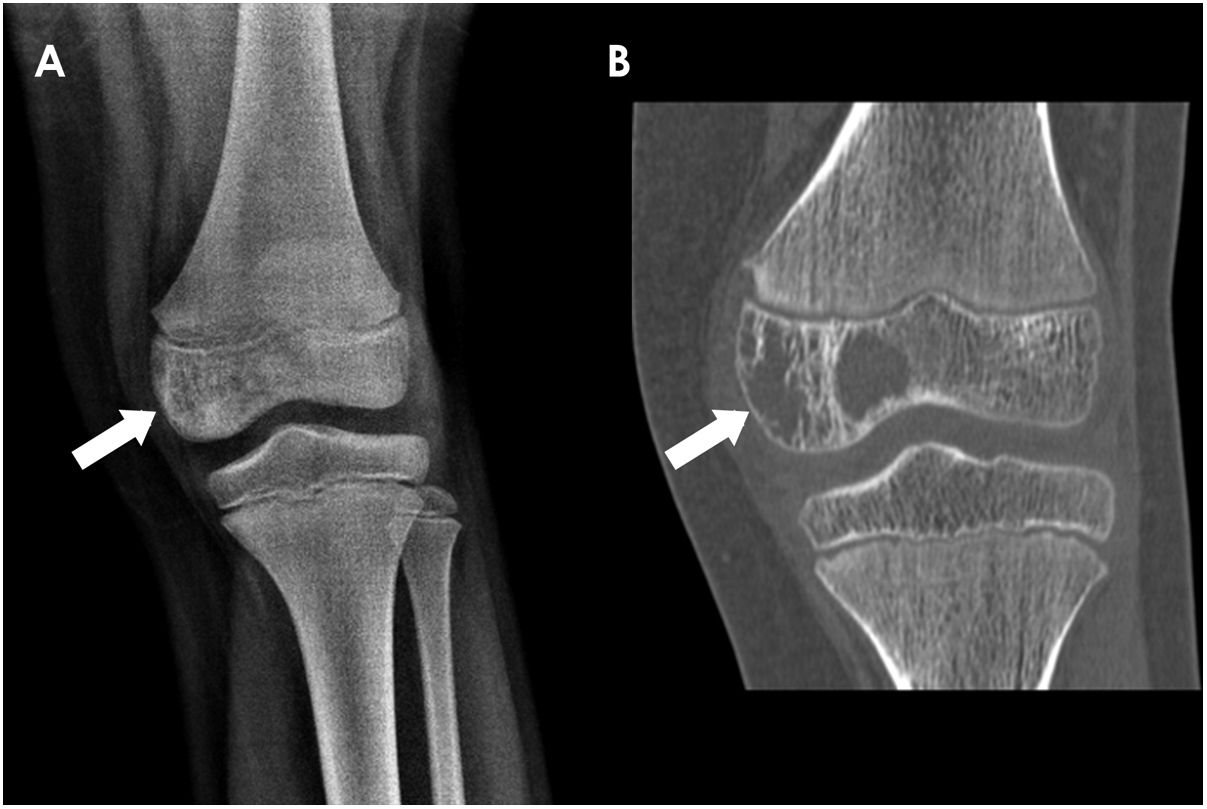

ResultsBoth tumours showed aggressive radiological features such as permeative or moth-eaten margins, cortical disruption, discontinuous periosteal reaction, intense contrast uptake, tumoral necrosis and soft-tissue component. They differed in their location, osseous matrix and gender predilection. Osteosarcoma occurred more frequently in the metaphysis of long bones (62%) with a blastic appearance (53%). Ewing sarcoma showed a predilection for male patients (71%), occurred in flat bones (42%) and in the diaphysis of long bones (58%) with a lytic appearance (82%). 29% of children presented with primary metastasis, most frequently located in the lungs. Survival rates were 78% in OS and 76% in Ewing sarcoma. Metastatic disease, aggressive radiological features and low percentage of tumoral necrosis after neoadjuvant chemotherapy were associated with poor prognosis (p < 0.05).

ConclusionsImaging can confidently diagnose malignant paediatric bone tumours in children and may differentiate Ewing sarcoma from osteosarcoma, based on gender, location and appearance of the neoplasm. Metastatic disease, presence of aggressive radiological features and low percentage of tumoral necrosis after neoadjuvant chemotherapy were associated with poor prognosis.